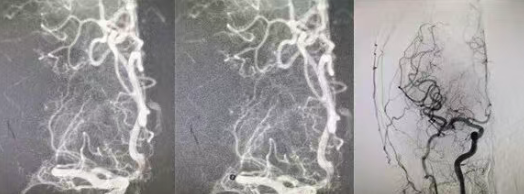

生死竞速!国文医院神经外科团队两次手术挽救颅脑重损伤患者生命

人生无常,世事难料。一场外出游玩,竟然被突如其来的意外改写了人生轨迹——年轻的患者意外摔伤了头部,剧烈的冲击造成严重颅脑损伤,他的生命体征急速下滑,如同风中残烛般岌岌可危。家人的呼救声里满是绝望,紧急送医的路上,时间每一秒都在与生命赛跑,最终,国文医院成了这场生死救援的“起点线”。 阅读量:196